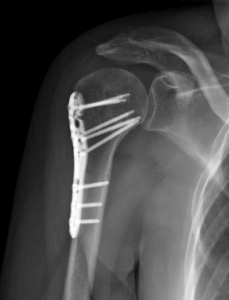

Dr. Riehl treats orthopaedic conditions both operatively and nonoperatively and performs a wide array of orthopaedic procedures including, but not limited to, the following:

Acute fracture care of the pelvis and the extremities